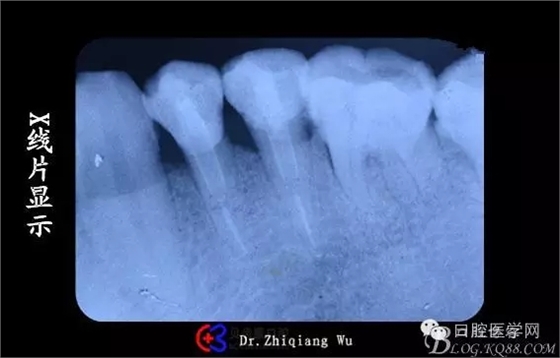

X線片顯示:34,35牙頸部大面積陰影,35根尖少量陰影

X線片顯示樁有點粗